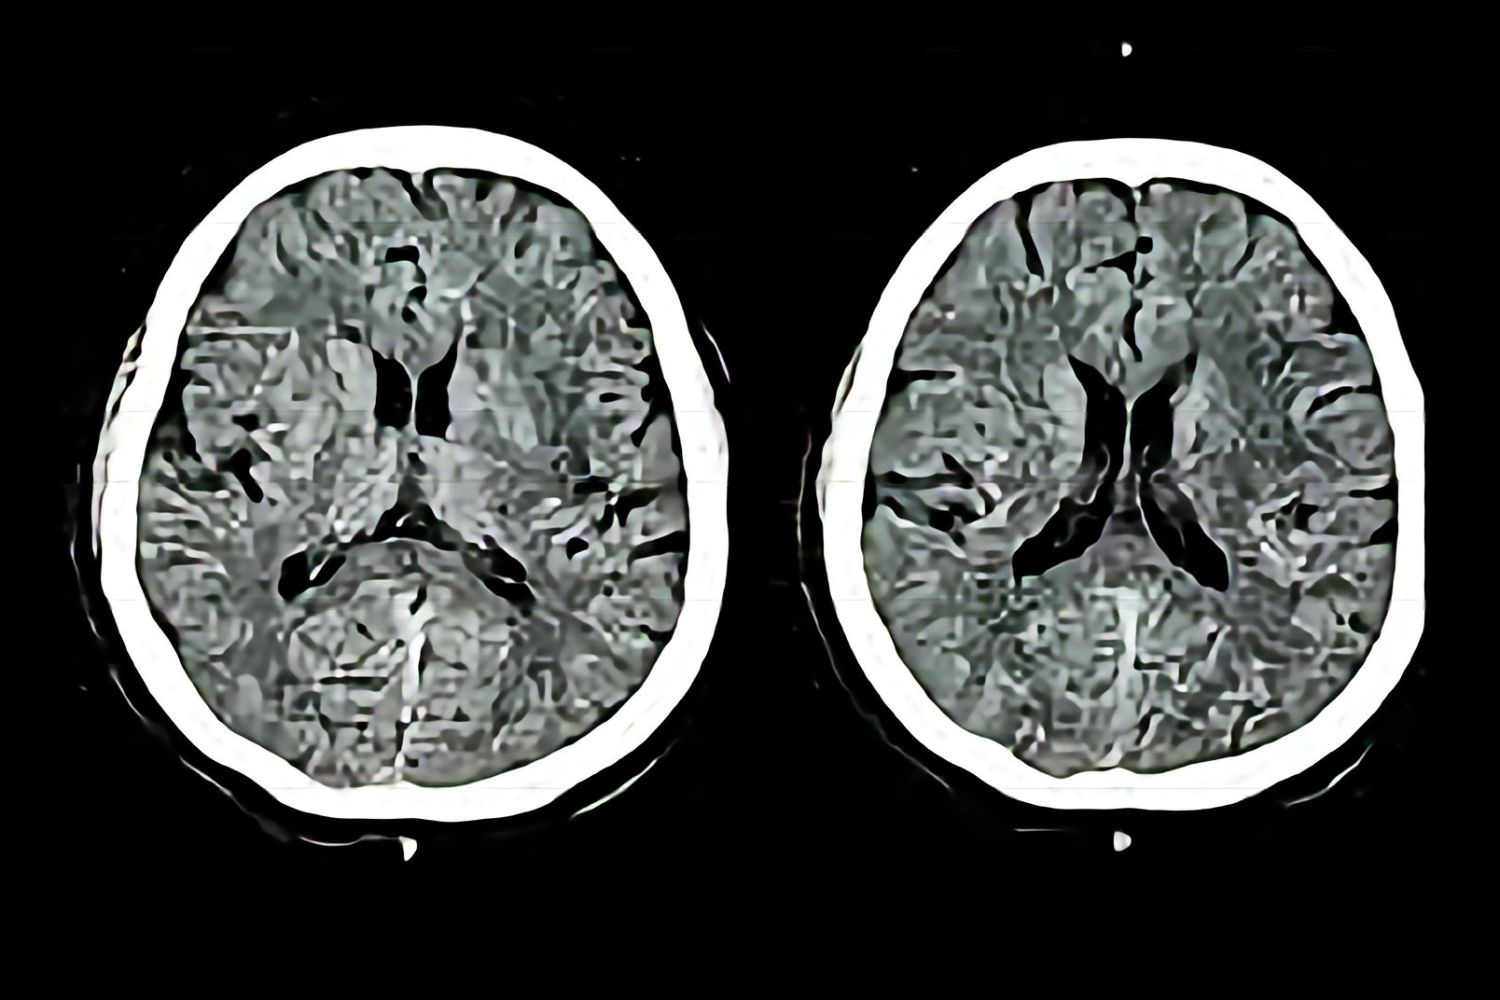

Para isso, utilizaram exames de ressonância magnética funcional antes e depois da experiência. Essa abordagem permitiu identificar alterações claras na atividade cerebral, revelando que o impacto da prática vai muito além da percepção subjetiva.

Uma das descobertas mais marcantes foi a redução da atividade em áreas do cérebro associadas ao diálogo interno constante. Esse fluxo contínuo de pensamentos, que muitas vezes prejudica a concentração, diminuiu significativamente.

No lugar desse padrão, surgiu um funcionamento mais focado e eficiente. Os participantes apresentaram maior capacidade de atenção e menos interferências cognitivas, o que sugere um aumento na plasticidade cerebral.

Isso significa que o cérebro se torna mais adaptável, reorganizando suas conexões de forma mais eficiente. Em outras palavras, ele aprende a funcionar melhor em menos tempo.